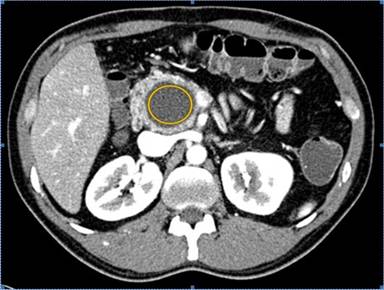

Image analysis was performed on a picture archiving and communication system (PACS) workstation (Centricity RA1000, GE HealthCare, Barrington, IL, USA) For each cystic lesion, attenuation was measured by drawing a circular or elliptical region of interest (ROI) (range: ROI area: 0.23-11.2 cm2, ROI pixels: 44-4,600) within the cyst’s greatest dimension in the trans-axial plane. Care was taken not to include the normal pancreatic tissue during placement of the ROI (Figure 1). Mean attenuation value (in Hounsfield units, HU) which represents the mean attenuation of all pixels within the ROI and maximum transaxial diameter of the cyst were recorded.

Figure 1. A 40-year-old man with pseudocyst in the head of the pancreas. Axial contrast-enhanced CT image exemplifies the cyst attenuation quantification by drawing ellipsoid region of interest (ROI). Care was taken to avoid the edges. Mean attenuation value, representing the mean attenuation of all pixels in ROI region, was recorded. |